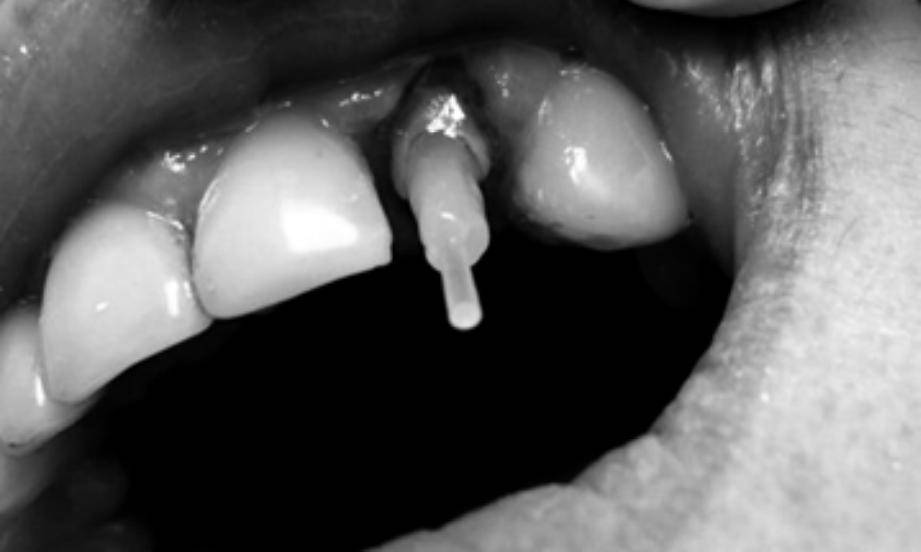

Постановка стекловолоконного штифта. Индивидуальный волоконный штифт пассивно вводится в корневой канал и проводится полимеризация композитного цемента. Далее полученное культевое ядро используем для проведения протезирования или в технике прямой реставрации.

Индивидуальный стекловолоконный штифт фото

Фиксация стекловолоконного штифта фото

Установка